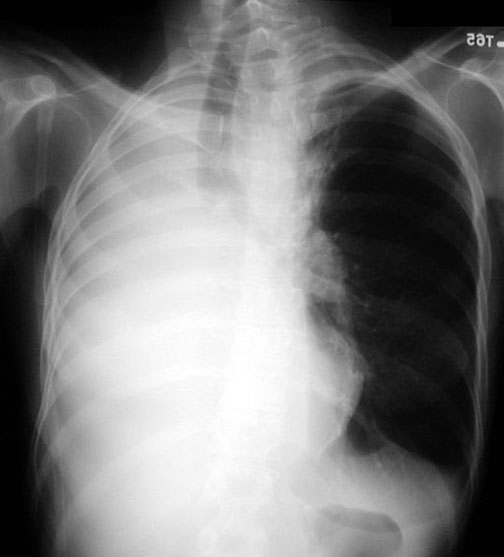

weekly clinical round for undergraduate from 8 to 11 AM during which interpretation of CHEST X rays was done for all cases of cardiothoracic surgery, gived by 2 staf member for 3 months